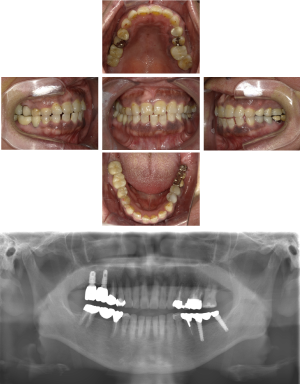

40代 女性 インプラント治療(GBR)

| 年代・性別 | 40代・女性 |

|---|---|

| 主訴 | 硬いものが咬めなくなってきたため、咬めるようになりたい。 |

| 部位 | 右上⑥5④ 右下6 上顎②11② |

| 治療期間 | 約1年2ヶ月 |

| 費用 | ¥2,099,900(税込) |

| 副作用・リスク |

|